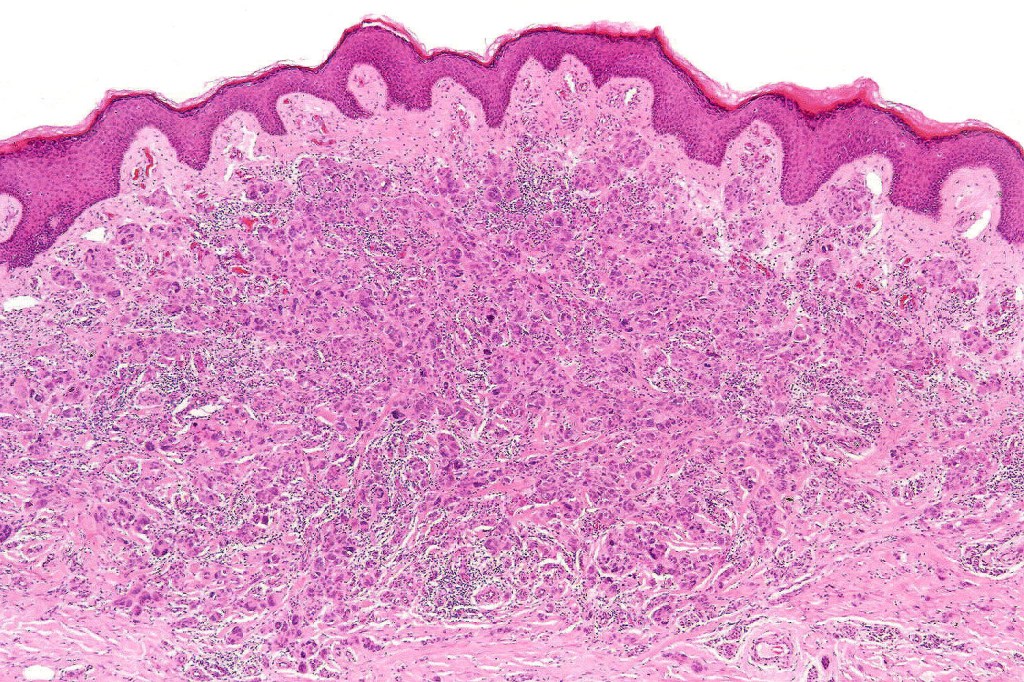

These are very rare variants of amelanotic or virtually amelanotic melanoma where a primary melanoma or a metastasis shows partial (DN) or complete loss (UN) of recognizable histological and immunohistochemical features. The histology may lead the pathologists to consider lymphoma, sarcoma, anaplastic carcinoma or a small cell tumor. Some examples of rhabdoid melanoma & melanoma with heterologous differentiation probably belong in this category. Ultimately, if there is no identifiable/recognizable primary tumor, diagnosis may only be comfortably made with next-generation sequencing. In the cases presented below, immunohistochemistry was of value in determining the melanoctic nature of the tumor (undifferentiated melanoma).